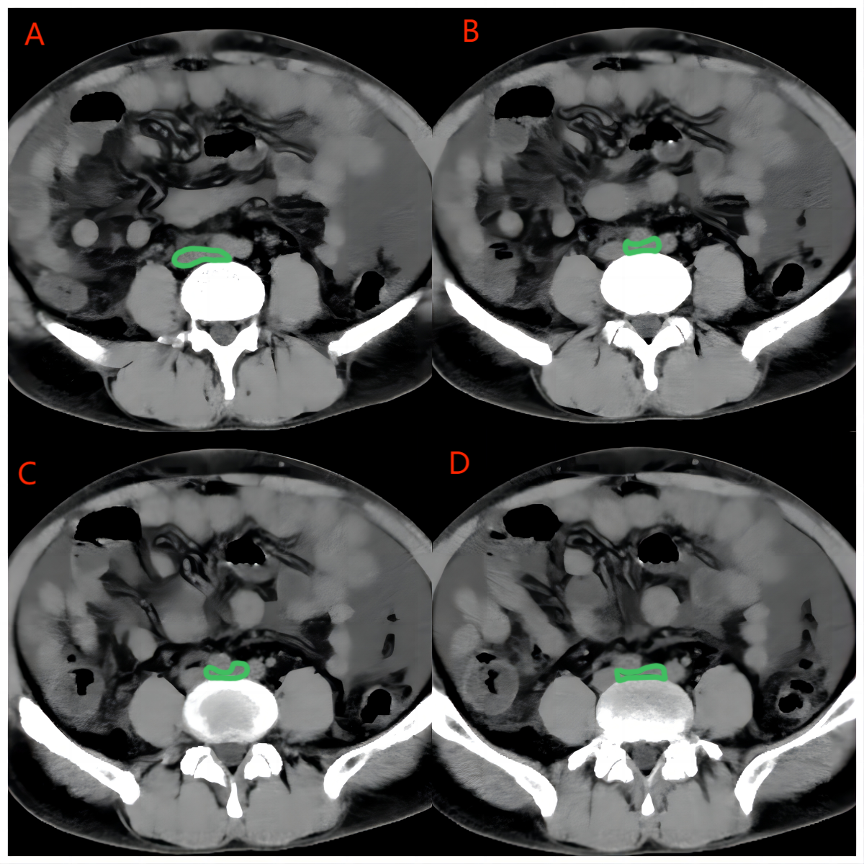

Refer to caption

Figure 4: Pic. A-B: The green mark is the bifurcation of the inferior vena cava, so that the left common iliac vein is significantly compressed by the right common iliac artery and the fifth lumbar spine; Pic. C-D: the left common iliac vein is significantly compressed, and the estimated stenosis rate is greater than 80%.